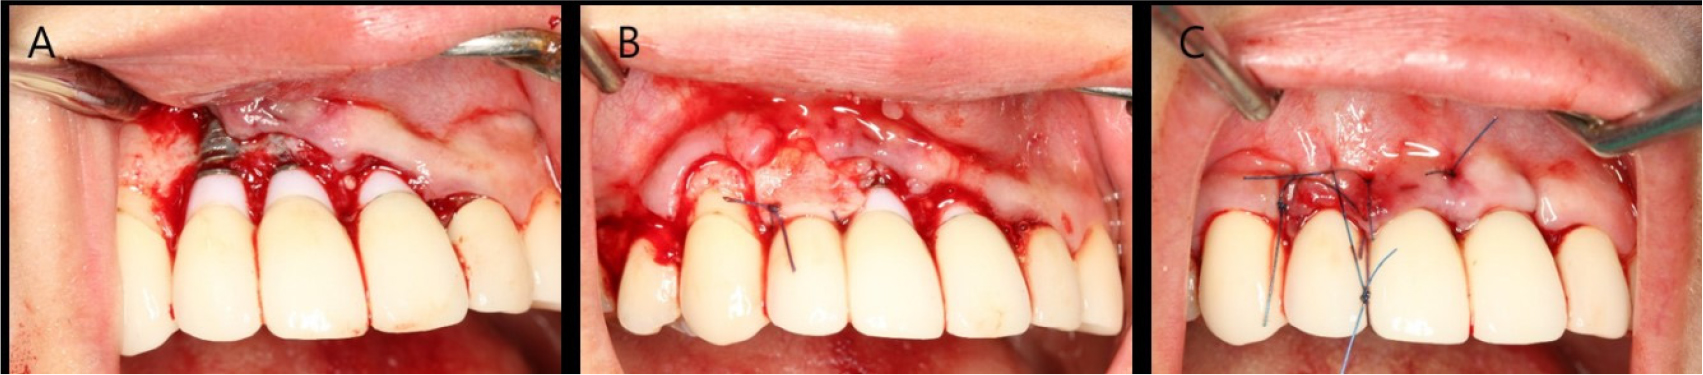

The patient was diagnosed with facial peri-implant soft tissue deficiency of the right maxillary lateral incisor. Soft tissue grafting was planned for gingival coverage of the exposed abutment. An intra-sulcular incision was made, and the flap was reflected. A bone dehiscence defect due to buccal bone resorption was observed. The exposed fixture was decontaminated using chlorhexidine ball scrubbing, titanium curettage and scaling, and saline irrigation. Subepithelial connective tissue was obtained from the palate using the trap door technique. Subepithelial connective tissue grafting was performed with a coronally advanced flap (Fig. 2).